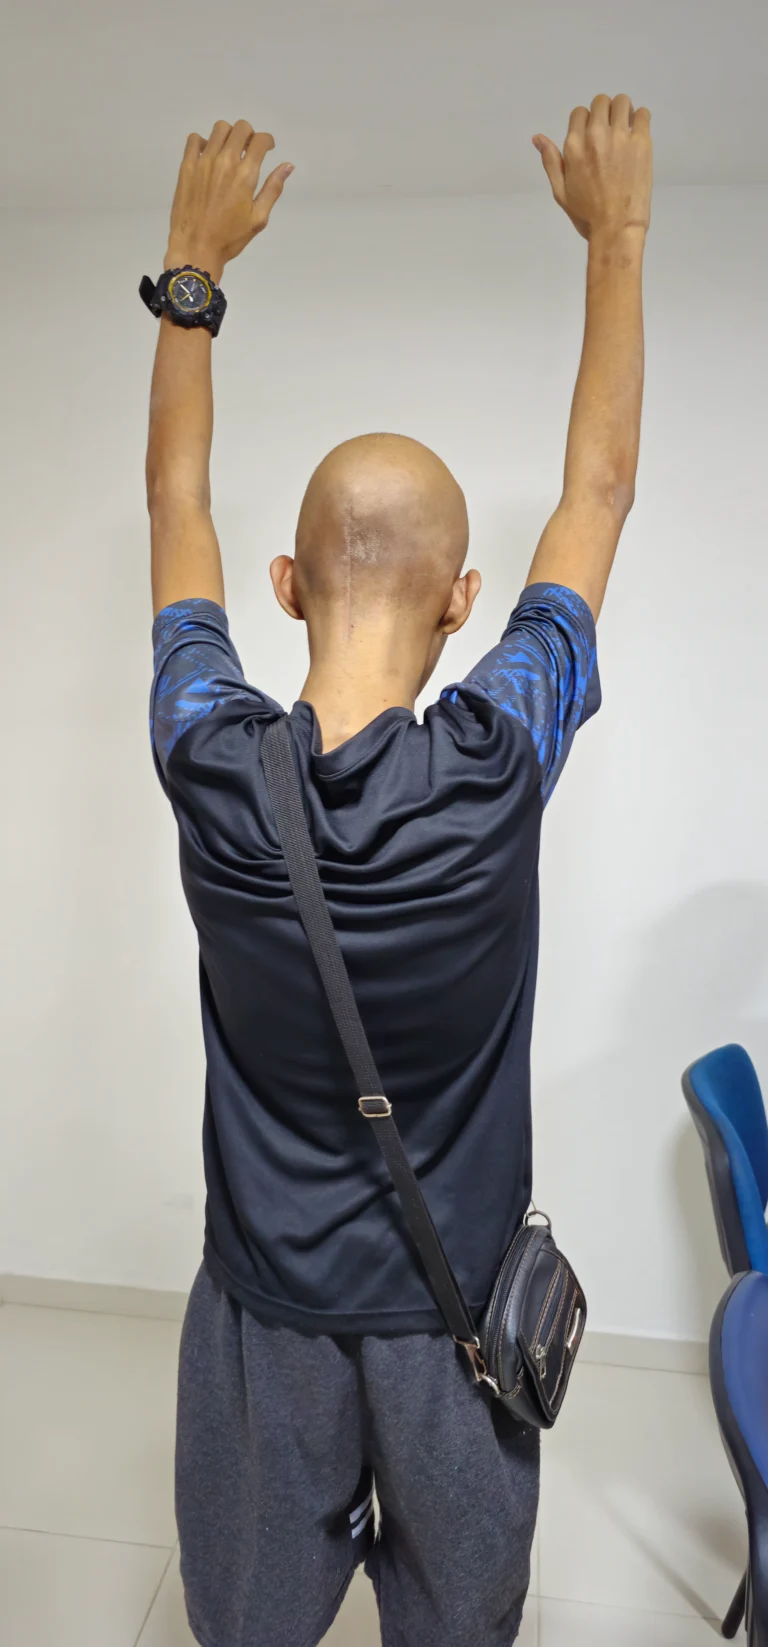

Specialist in the diagnosis and surgical management of conditions of the nervous system, with expertise in minimally invasive spine surgery, skull base procedures, neuro-oncology, and complex cranial and spinal pathologies.

- ✔ Minimally Invasive Spine Surgery

- ✔ Pediatric Neurosurgery

- ✔️ Minimally invasive spine surgery

- ✔️ Pediatric neurosurgery